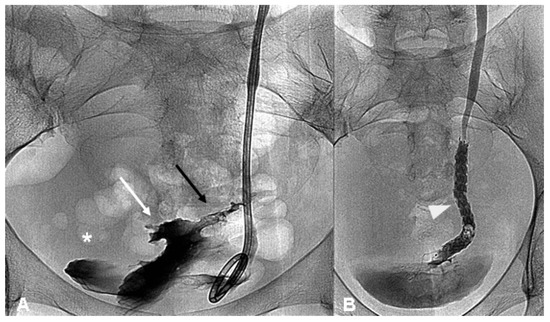

Stent replacement/removal was managed in the angiography suite using a retrograde technique (Figure 3A–D) as previously described [12] at 1, 3 and 6 months, and then every 6 months. A retrograde pyelography and a CBCT scan were performed in all cases to verify the restored integrity of the injured ureter at every control after DJ stent removal before making a decision about for a new DJ stent placement; ureteral continuity was ensured by a guidewire during this diagnostic phase.

Figure 3. (AD)—Double J stent substitution and ureteral ballooning. The distal end of the right ureteral double J stent is grasped with a goose-neck snare catheter (white arrow head) positioned in the lumen of the opacified bladder under fluoroscopic guidance (A); ascending pyelography through a vascular 7 Fr introducer shows a residual stenosis (white asterisk) at the distal portion of the right ureter (B); ureteral dilatation procedure is performed using 6 × 40 mm balloon (black harrow) (C); a new double-J stent was inserted and correctly positioned (D).